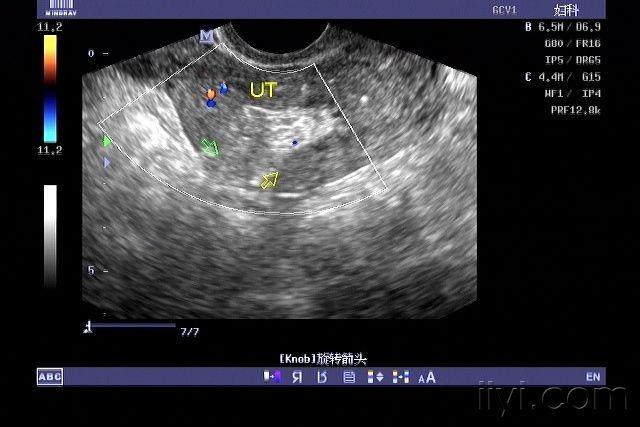

子宫穿孔的超声诊断

超声典型病例子宫穿孔

子宫穿孔彩超下表现

子宫穿孔超声表现图